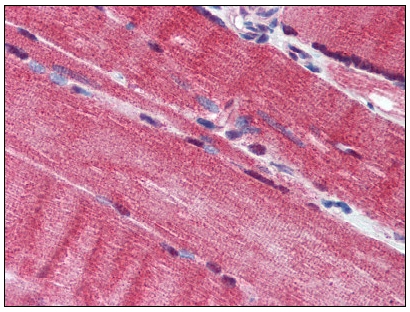

| Applications | IHC, WB |

| Recommended Dilution | Immunohistochemistry on Paraffin Sections: 10 µg/ml. Western Blot: 1 - 3 µg/ml. |

| Reactivities | Canine, Human, Mouse, Rat |